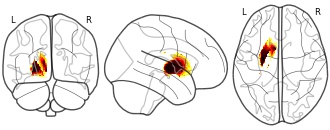

coco_mcgill's temporary collection: coco

- neurovault.org

EmailClick to copy linkLink copied Cite(2021). coco_mcgill's temporary collection: coco [Dataset]. http://identifiers.org/neurovault.image:441996niftiAvailable download formatsUnique identifierhttps://identifiers.org/neurovault.image:441996Dataset updatedFeb 15, 2021License

Cite(2021). coco_mcgill's temporary collection: coco [Dataset]. http://identifiers.org/neurovault.image:441996niftiAvailable download formatsUnique identifierhttps://identifiers.org/neurovault.image:441996Dataset updatedFeb 15, 2021LicenseCC0 1.0 Universal Public Domain Dedicationhttps://creativecommons.org/publicdomain/zero/1.0/

License information was derived automaticallyDescriptionCollection description

None

Subject species

homo sapiens

Modality

Structural MRI

Cognitive paradigm (task)

None / Other

Map type

R

License information was derived automaticallyDescriptionThe data for this project is part of the Natural Scenes Dataset (NSD), a massive dataset of 7T fMRI responses to images of natural scenes coming from the COCO dataset. The training dataset consists of brain responses measured at 10.000 brain locations (voxels) to 8857 images (in jpg format) for one subject. The 10.000 voxels are distributed around the visual pathway and may encode perceptual and semantic features in different proportions. The test dataset comprises 984 images (in jpg format), and the goal is to predict the brain responses to these images.